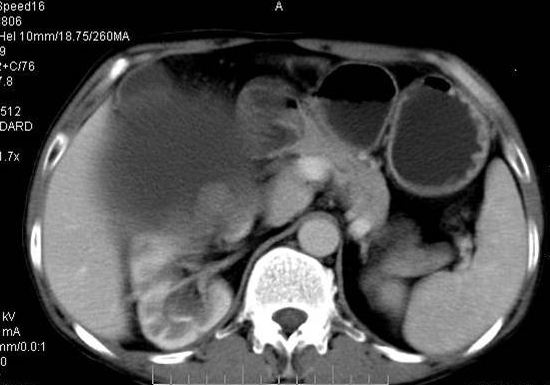

男性 60岁,腹部肿块4年余,肿块逐渐增大,活动性差,无血尿。

动脉期

巨大囊性肿块,囊壁较厚有强化,有团片状钙化,病灶内下方灶内见片絮状高密度影,增强有轻中度强化,考虑囊性肾癌可能性大

右肾上部巨大的囊实性影,实性部分轻度强化。壁有钙化。考虑右肾囊腺癌。右肾盂积水。

定位;肾明显与病灶杯口相交,可以肯定病变来自右肾。

定性;病灶囊性为主,前下部含实性成分,及钙化,部分壁厚薄不均。

肾囊实性病变有;1,囊性肾癌2,囊性肾瘤。3,复杂囊肿。4,重复肾伴积水。然2、3壁相对规则。

综上考虑;囊性肾癌》重复肾伴积水。